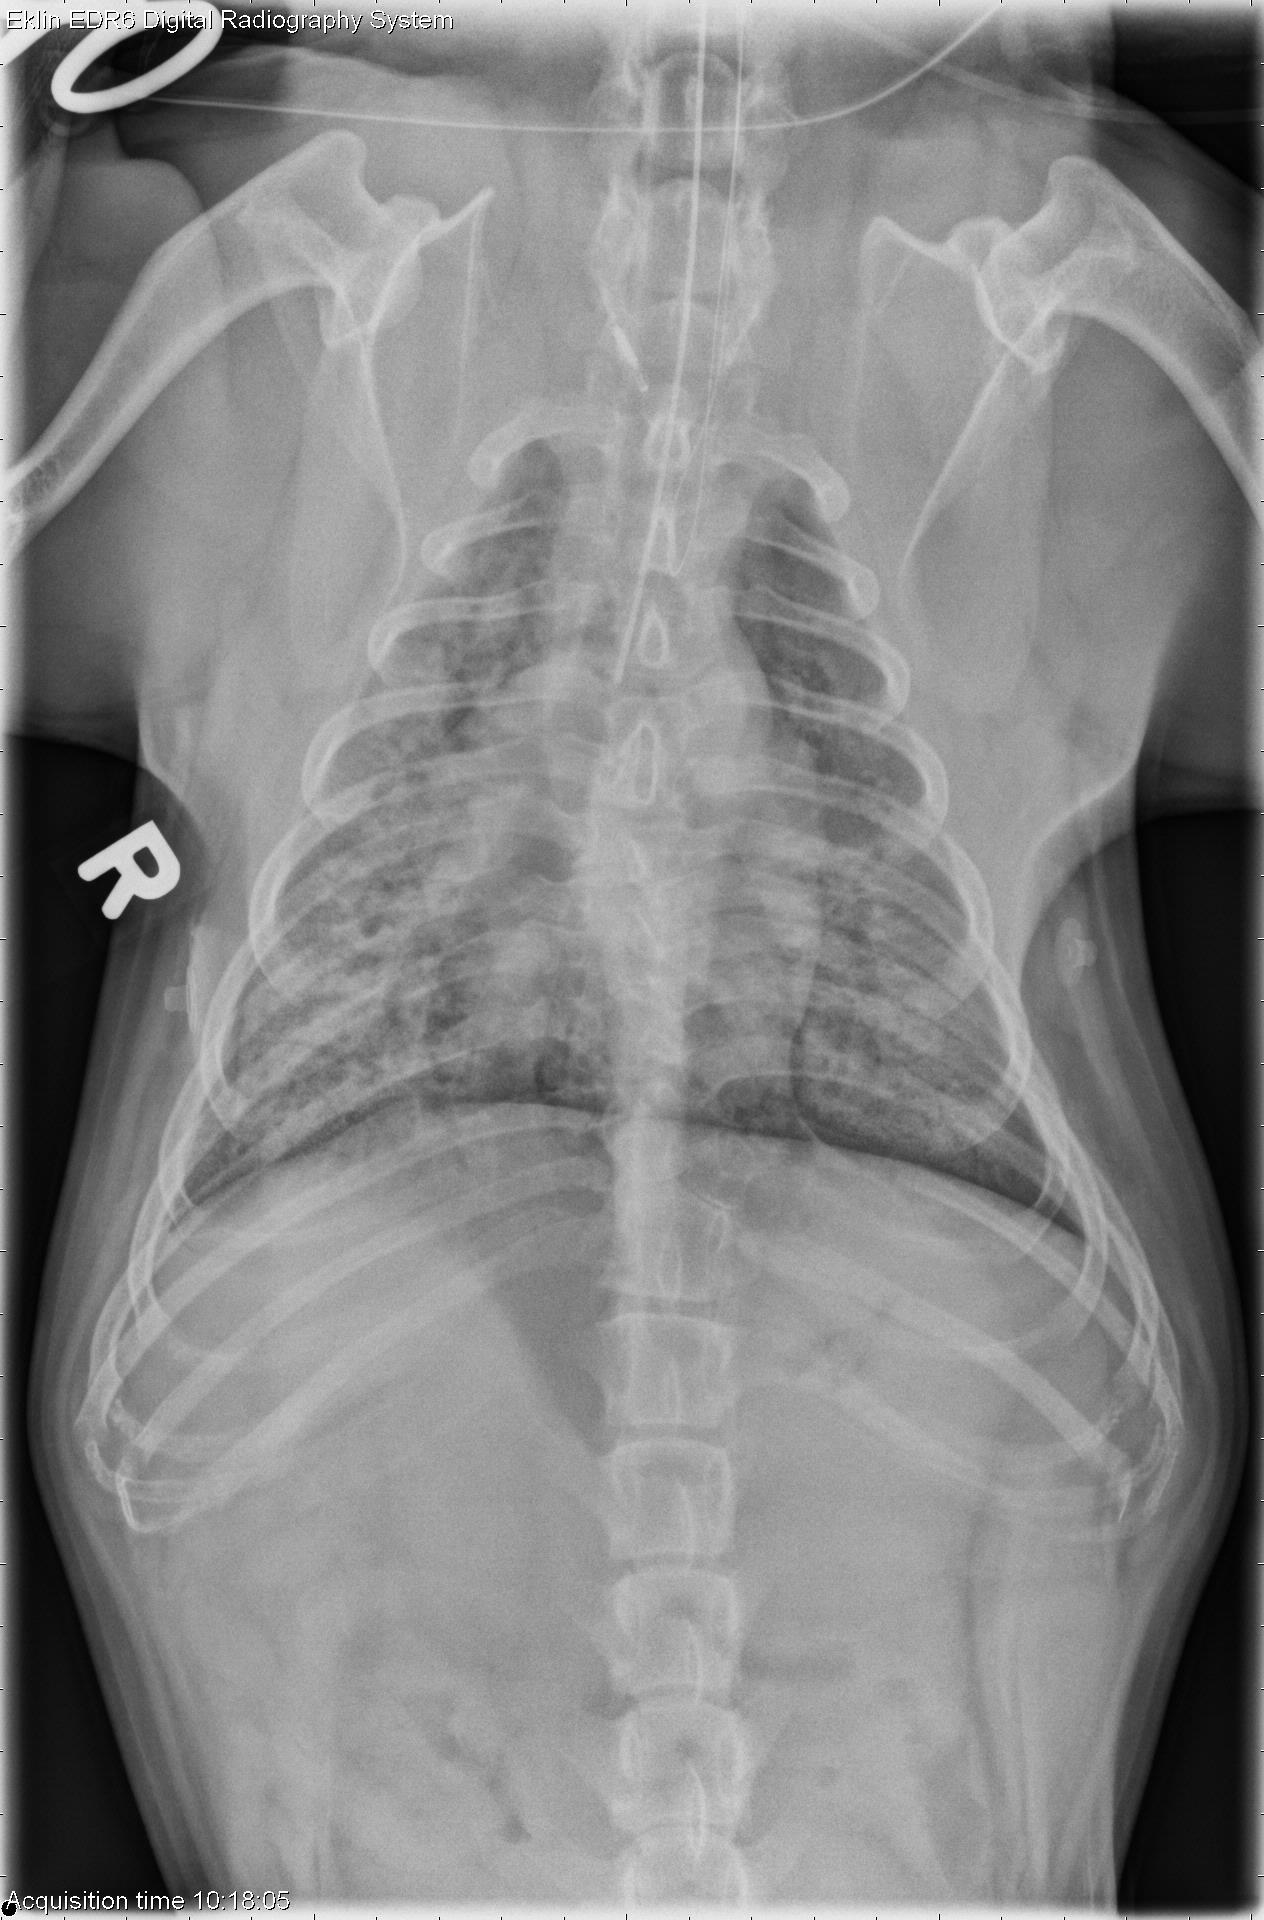

From www.veterinaryradiology.net

4 year old French bulldog Dip In French Bulldog Spine the existence of many spine diseases, e.g., hemivertebrae, degenerative myelopathy, and slipped disc disease, makes understanding each of them very important, particularly as an owner. Intervertebral disc disease (ivdd) is common in french bulldogs. ivdd is a serious condition that can affect french bulldogs. what is intervertebral disc disease (ivdd)? ivdd in french bulldogs can be. Dip In French Bulldog Spine.

poor french bulldog spine _ feel so bad for these dogs r/Radiology Dip In French Bulldog Spine the disease occurs when the cushioning discs between the vertebrae of the spinal column either bulge or burst (herniate) into the spinal cord space. As the name suggests, it affects the intervertebral disc. ivdd is a serious condition that can affect french bulldogs. Intervertebral disc disease (ivdd) is common in french bulldogs. intervertebral disc disease, commonly known. Dip In French Bulldog Spine.